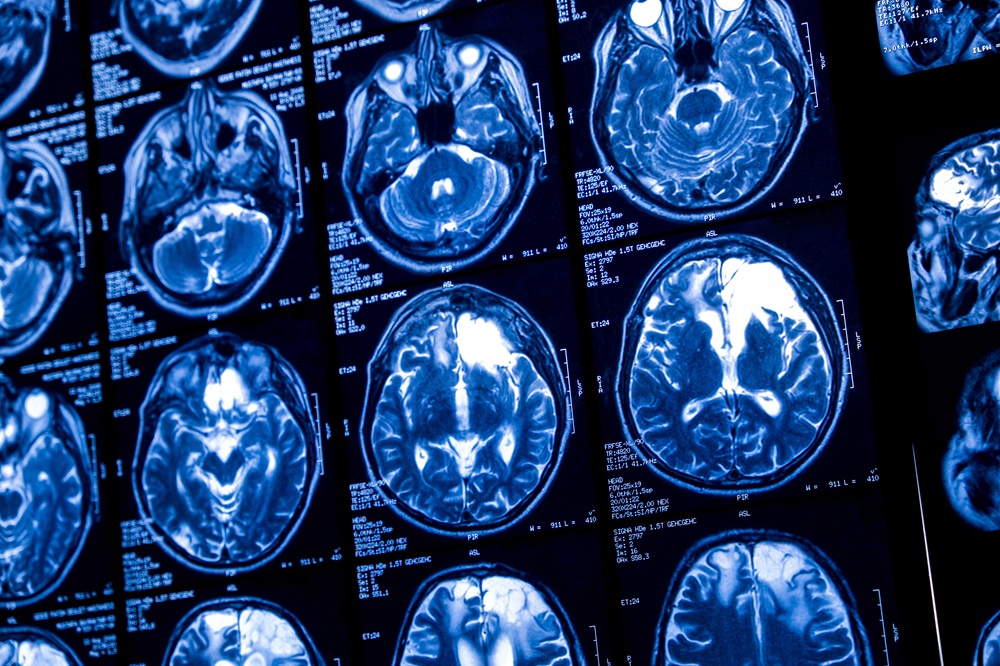

MRI scans also revealed former players had reduced brain volume in some areas, compared with the control group.